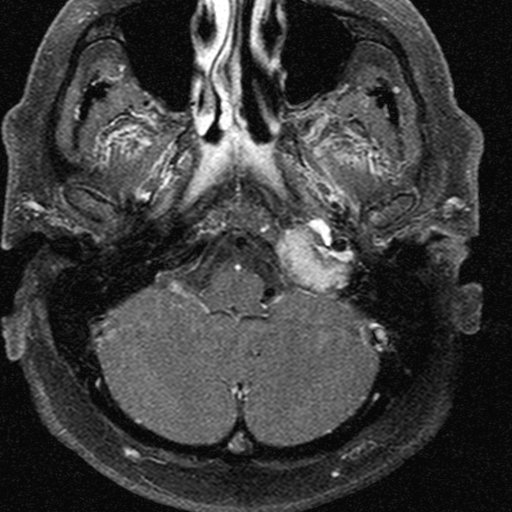

4. image: Young male patient with a left supraclavicular lump. Upper panel: complex cystic mass with sepatations; normal flow in the neighbouring vessels. Lower panel: T2W, postcontrast T1W, fat-saturation T1W MRI suggest cystic lymphangioma (Asklepios Klinik Altona, Hamburg)